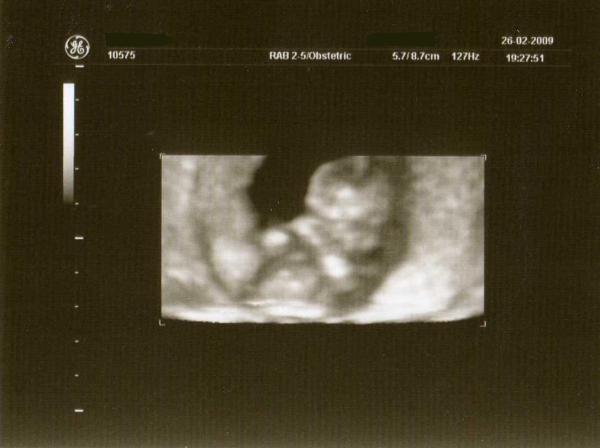

hallo, wollte mal hören, wie groß euer Kleines in der 14 ssw war. Fahre im Septembert-Bus mit und hatte eine VU am Donnerstag. Könnt Ihr mir vielleicht auch sagen, was es evt. sein kann (Junge oder Mädchen)?